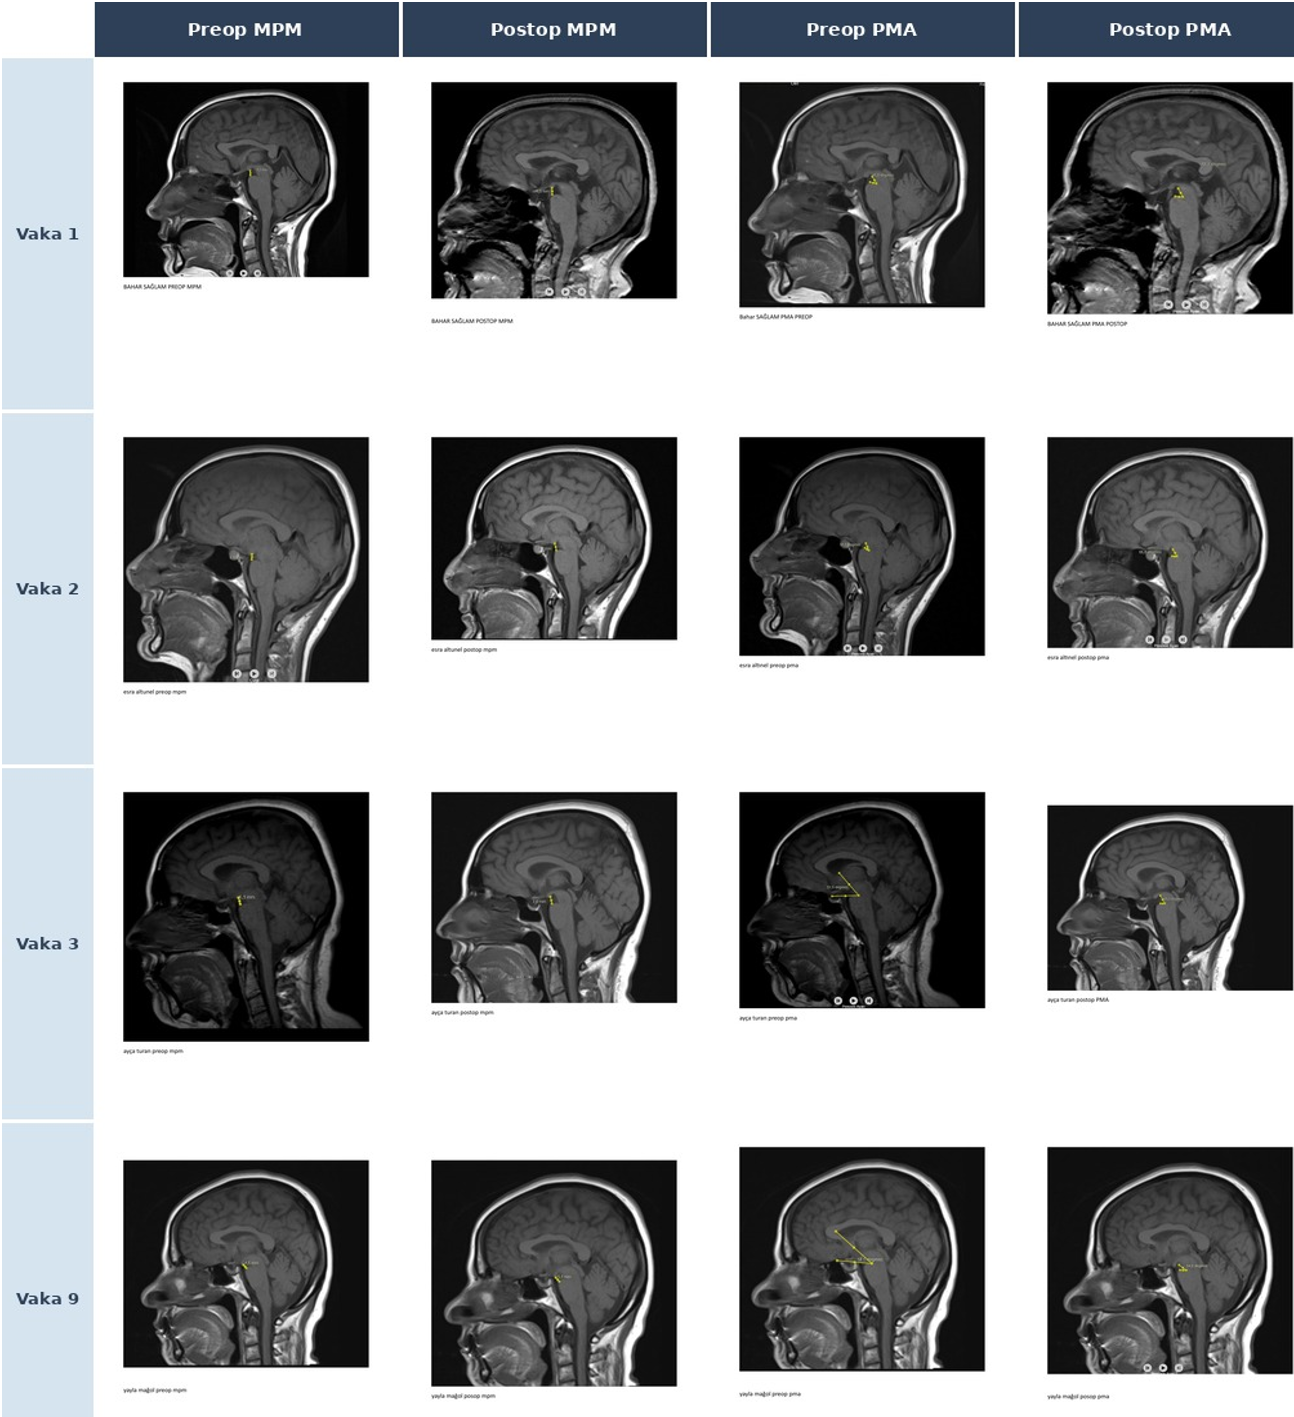

Kranyal MRG bulguları Bern SİH kranyal MRG skorlama sistemi7 kullanılarak sistematik olarak değerlendirildi (pakimeningeal kontrast tutulumu, venöz sinüs distansiyonu/VDİ, subdural sıvı koleksiyonu, suprasellar sisterna, prepontin sisterna ve hipofiz büyümesi; toplam 0–9 puan). PMA, sagittal T1 MRG’de mezensefalon dorsal yüzeyi ile pons ventral yüzeyi arasındaki kesişim açısı olarak ölçüldü (normal 55–75°; EKY yanıt eşiği ≥40°).9 MPM, midsagittal T1’de mamiller cismin alt ucundan ponsa dik mesafe olarak tanımlandı. CXA, sagittal BT görüntülerinde klivus posterior yüzeyi boyunca çizilen hat ile C2 aksı arasındaki açı olarak ölçüldü (normal >135°). VDİ, orijinal tanımına uygun şekilde kaydedildi.13 Tüm ölçümler tek bir araştırmacı tarafından retrospektif olarak yapıldı. PMA ve MPM ölçüm teknikleri Şekil 2’de gösterilmektedir.

Ölçüm yapılabilen yedi hastada (Vakalar 1–5, 8–9) preoperatif PMA 27,4°–37,5° arasında dağıldı; tüm değerler normal referans aralığının (55–75°) ve Wu ve ark.’nın EKY yanıt eşiğinin (≥40°)9 belirgin altındaydı. MPM 3,3–4,6 mm (normal ~9–12 mm), CXA 141,5°–167,3° arasında saptandı (Şekil 3). Venöz distansiyon işareti (VDİ) sekiz hastada (%88,9) pozitifti. Postoperatif görüntüleme mevcut olan dört hastada (Vakalar 1, 2, 3, 9) en belirgin PMA artışı Vaka 3’te gözlendi (+17,4°); ancak hiçbir hastada normal referans aralığına ulaşılamadı. Vaka 9’da üç ardışık EKY sonrasında klinik iyileşme elde edilmesine karşın PMA hafifçe geriledi (37,5°→34,6°). Tüm ölçümler Tablo 2 ve Tablo 3’te özetlenmiştir (Şekil 4).

Bern skoru, PMA ve etiyolojik alt tip arasında tutarlı kümelenme gözlemlendi: CVF olguları (Vakalar 6–7) en yüksek Bern skoru (9) ve ölçülemeyen PMA ile ağır fenotipi temsil ederken, kriptojenik olgu Vaka 3 en düşük Bern skorunu (2) ve en belirgin radyolojik iyileşmeyi (%17,4° PMA artışı) gösterdi. İstatistiksel analiz özeti Tablo 4’te verilmektedir. Prepontin ve suprasellar sisterna ölçümleri Şekil 5’te sunulmaktadır.